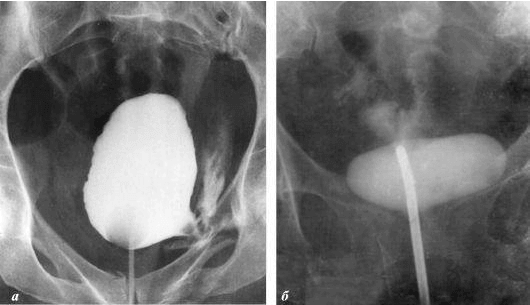

Ich möchte Ihnen ein paar Fotos zeigen, um zu zeigen, was im Urogenitalsystem und anderen Organen eines Mannes vor sich geht, der keinen Sex hat.

So sieht eine Entzündung der Prostata aus, die durch Stagnation der Spermien verursacht wird (wenn die Hoden nicht geleert werden). Eine anhaltende Entzündung führt zuerst zu einem Prostataadenom und dann zu Krebs. Dies ist eine unvermeidliche Folge von Prostatitis, daher wird es als "Krankheit der älteren Generation" bezeichnet.

Prostatakrebs bei einem Mann mit 58 Jahren.